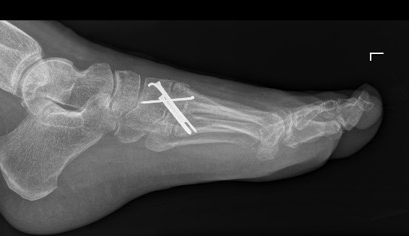

Surgery for midfoot arthritis ranges from simple to more complex procedures. Surgery may involve a “clean-up” of the joint by removing damaged cartilage and bone spurs, resection of a part of the joint, fusion (stiffening) of one or more joints. Medical imaging, such as x-rays and MRIs are usually obtained prior to surgery to determine the extent of the injury and to plan for the proposed surgery.